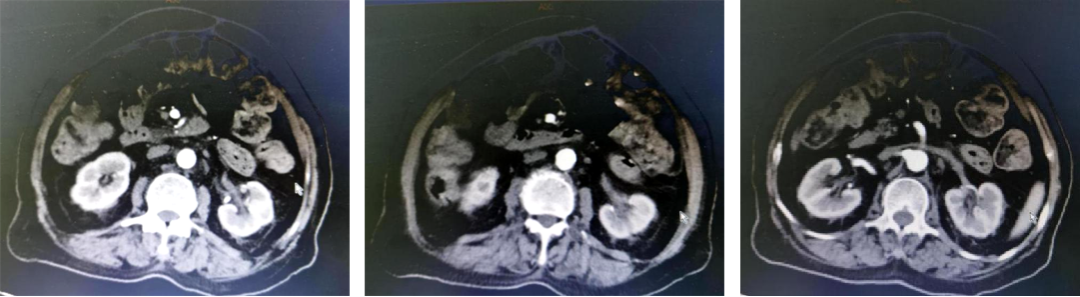

基本信息:性别 女,年龄 78岁,身高 159cm,体重 62kg。 主诉:结肠癌及肝转移瘤术后2年6个月(首次就诊时间为2018-09-10)。 既往史、个人史:“2型糖尿病”20年,予“二甲双胍 0.5g 口服 2次/日、门冬胰岛素注射液皮下注射,早 30U,晚 28U;甘精胰岛素皮下注射 20U ”降糖治疗,血糖控制一般。 家族史:无特殊。 02 初诊病史 体格检查、B超、CT及其他辅助检查。 体表面积1.60m,体格检查:浅表淋巴结未及肿大,双肺呼吸音粗,未闻及干湿性啰音,心律规整,未闻及杂音,腹壁可见陈旧性手术瘢痕,愈合良好,腹软,未及肿物,无压痛,肛查-,双下肢无水肿,起病隐匿,体检行腹部超声发现肝脏占位。 肠镜(2016-3-12):乙状结肠肿物。 咬检病理:(乙状结肠)腺癌。 肝胆胰增强CT(2016-3-10):肝左叶占位。 考虑:乙状结肠癌Ⅳ期 肝转移。 2016-3-21 于外院行“乙状结肠癌根治术+肝左叶转移瘤切除术”,术中予输血治疗,术后恢复慢,切口延期愈合。 术后病理:结肠中分化腺癌伴坏死形成,大者3.5cm×3.2cm×0.5cm,癌组织侵及浆膜脂肪层,脉管内癌栓形成,小者1cm×1cm×0.5cm,癌组织侵及粘膜下层。肠壁周围淋巴结癌转移(3/6),T3N1M1。(肝左叶)肝脏转移性腺癌伴大片坏死形成,大小6.6cm×6cm×4.5cm,结肠来源,残端及吻合口上下缘肠壁未见肿瘤侵及。 基因检测:KRAS、NRAS、BRAF 均未见突变。 初步诊断:乙状结肠癌Ⅳ期(pT3N1M1),同时性肝转移,中分化腺癌,2型糖尿病。 03 治疗方案 2016-4 XELOX 方案化疗1周期(具体剂量不详)因不良反应较重,未完成术后辅助治疗疗程。未予后续治疗,定期复查,病情稳定 胸腹CT(2017-3-19 ):右肺下叶新结节,考虑转移;肝左外叶转移瘤切除术后改变。 2017-4-1 于外院行局部肺肿物射频消融术,无治疗反应,恢复良好。 胸CT(2017-12-5):肺部新发结节,考虑转移。 【一线治疗方案(2017-12至2018-9)】 卡培他滨 1.5g po d1-14 q3w,共10个周期。 不良反应:1度消化道反应。 期间疗效评价:SD。 胸腹增强CT(2018-9-11):符合结肠癌切除术后,肝左叶切除后改变,双肺多发结节,部分较前增大。 2017-12-5 2018-9-11 建议调整方案治疗,患者家属拒绝,继续口服卡培他滨至2019年3月。 疗效评估: ECOG PS评分1分,新发活动后胸闷、气短症状 胸腹平扫CT(2019-3-26):双肺多发结节,较前增大;肝左外叶转移瘤切除术后改变。 2018-9-11 2019-3-26 评估PD。 【二线治疗方案(2019-4至2020-5)】 贝伐珠单抗 300mg ivgtt d0(体重62kg); 卡培他滨 1.5g po d1-14 q3w,共15周期。 不良反应:1级高血压、1度消化道反应。 疗效评估: 胸腹CT(2020-5-21):符合结肠癌术后、肝左叶切除术后,肝左切缘旁异常密度灶,左髂总动脉旁淋巴结;双肺多发结节,部分较前增大,右肺门肿物较前增大。 疗效评价:PD。 【三线治疗方案(2020-5至2020-10)】 西妥昔单抗 600mg ivgtt d0(体表面积1.66 m2); 亚叶酸钙 500mg ivgtt d1; 氟尿嘧啶 500mg ivgtt ,随后3500mg iv泵入 q2w,共9周期。 不良反应:无皮疹、腹泻、恶心、呕吐等。 疗效评估: 胸腹平扫CT(2020-09-07):右肺下叶背段软组织肿块,较前略减小,双肺多发小结节,转移瘤,同前;结肠癌术后、肝左叶切除术后改变,肝左切缘旁异常密度灶同前相仿,腹膜后左侧髂总动脉旁淋巴结同前。 2020-7-23 2020-9-7 疗效评价:SD(缩小趋势)。 胸腹平扫CT(2020-10-24):右肺下叶背段软组织肿块,较前(2020-9-7)略减小,双肺多发小结节,转移瘤,部分较前减小,结肠癌术后、肝左叶切除术后改变,肝左切缘旁异常密度灶同前相仿,腹膜后左侧髂总动脉旁淋巴结同前。 2020-9-7 2020-10-24 疗效评价:SD(缩小趋势)。 胸腹平扫CT(2020-12-13):右肺下叶背段软组织肿块,较前(2020-10-24)未见著变,双肺多发小结节,转移瘤,较前未见著变,结肠癌术后、肝左叶切除术后改变,肝左切缘旁异常密度灶同前相仿,腹膜后左侧髂总动脉旁淋巴结同前。 2020-12-13 疗效评价:SD。 患者未规律返院行西妥昔单抗维持治疗。 胸腹增强CT(2021-1-5):右肺下叶背段软组织肿块,较前(2020-12-13)增大,双肺多发小结节,转移瘤,左肺尖结节较前增大,余未见著变,左侧髂总动脉旁淋巴结较前增大。 疗效评价:PD。 【四线治疗方案(2021-1至2021-10)】 安罗替尼 8mg po 1次/日 d1-14 (2021-3 起因高血压2级,药物控制不佳调整为8mg qod ); 卡培他滨 1g po 2次/日 d1-14 q3w (2021-4 起因乏力2级不能耐受停服)。 不良反应:2级高血压,2级乏力,1级胆红素升高,1度消化道反应。 疗效评估: 胸腹增强CT(2021-10-3):右肺下叶背段占位,考虑恶性肿瘤,较前增大,双肺多发转移瘤,部分较前略增大,结肠癌术后、直肠区肠管明显扩张,肝左叶切除术后改变,切缘旁占位伴肝内胆管扩张,累及胆总管,考虑恶性病变,较前增大,腹膜后左侧髂总动脉旁淋巴结,较前增大,累及左侧输尿管伴以上输尿管及肾盂扩张。 2021-10-3 疗效评价:PD。 疗效评估: 胸腹增强CT(2021-10-3):右肺下叶背段占位,考虑恶性肿瘤,较前增大,双肺多发转移瘤,部分较前略增大,结肠癌术后、直肠区肠管明显扩张,肝左叶切除术后改变,切缘旁占位伴肝内胆管扩张,累及胆总管,考虑恶性病变,较前增大,腹膜后左侧髂总动脉旁淋巴结,较前增大,累及左侧输尿管伴以上输尿管及肾盂扩张。 【后线治疗方案(2021-10至2021-11)】 曲氟尿苷替匹嘧啶片(TAS-102) 40mg po 2次/日 d1-5,d8-12,q4w; 贝伐珠单抗 200mg ivgtt q2w。 不良反应:无皮疹、腹泻、恶心、呕吐等。 疗效评估: 胸腹增强CT(2021-11-17):右肺下叶背段占位,较前变化不明显,双肺多发转移瘤,较前变化不明显,结肠癌术后、直肠区肠管明显扩张,肝左叶切除术后改变,切缘旁占位伴肝内胆管扩张,累及胆总管,考虑恶性病变,较前变化不明显,腹膜后左侧髂总动脉旁淋巴结,较前减小,肾盂扩张较前减轻。 疗效评价:SD。 胸腹增强CT(2021-11-17):右肺下叶背段占位,较前变化不明显,双肺多发转移瘤,较前变化不明显,结肠癌术后、直肠区肠管明显扩张,肝左叶切除术后改变,切缘旁占位伴肝内胆管扩张,累及胆总管,考虑恶性病变,较前变化不明显,腹膜后左侧髂总动脉旁淋巴结,较前减小,肾盂扩张较前减轻。 04 病例小结 患者为高龄女性,诊断为直肠癌Ⅳ期多发转移,KRAS、NRAS、BRAF 均未见突变。 OS为69个月。